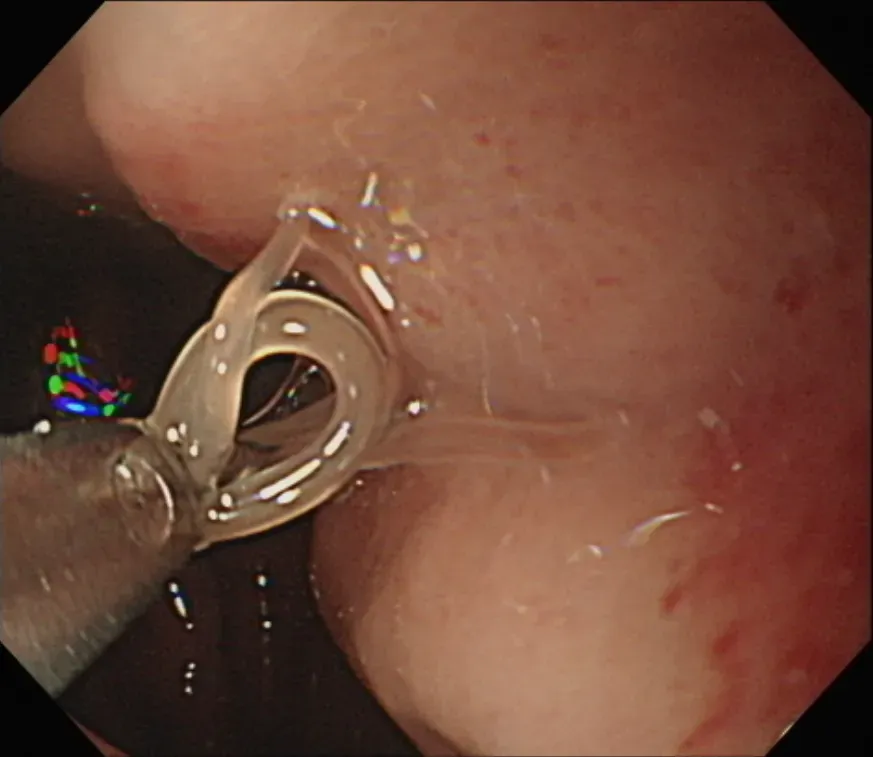

愛吃生魚片!50歲男照胃鏡驚見「5公分海獸胃線蟲蠕動」

海獸胃線蟲

生魚片

寄生蟲

蠕動

照胃鏡

影/饕客注意!他爽吃生魚片、烏賊 慘遭「冬粉狀寄生蟲」入侵

烏賊

胃鏡檢查

賁門